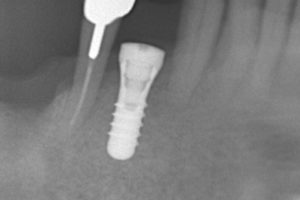

これは本日の手術直後のレントゲン写真です。

最小限の歯茎を切開することで実際の手術時間は30分程度で終了です。

手術直後ですが、ほとんどの患者様は1回痛み止めを服用する程度で、今回の患者様は手術中はうたた寝されておりました(^^♪

このように、しっかりとした診査・診断のもと、手術を行うことで、手術時間の短縮・その後の腫脹・痛みの軽減に全力で取り組んでおります。また、当院で使用しているインプラントはストローマンという、世界で多くの歴史・実績があるものを使用しており、私院長も多大な信頼を持っております。